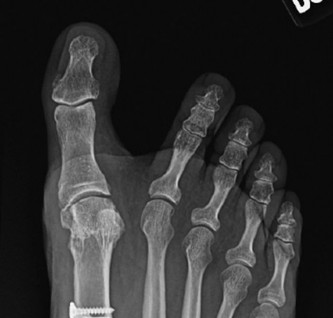

Medial Eminence Resection Bunionectomy

- Identification of the Eminence: The hypertrophied medial aspect of the first metatarsal head is clearly identified.

-

Resection Plane: This is the most critical step for avoiding hallux varus and recurrence.

- The cut should be made parallel to the medial shaft of the first metatarsal, extending distally.

- The resection should remove the prominent bone but not extend into the sagittal groove where the sesamoids articulate plantarly. Over-resection into this groove destabilizes the sesamoids and significantly increases the risk of hallux varus.

- The cut should ideally be just medial to the articular cartilage of the metatarsal head, preserving the cartilage surface.

- Technique: Use an oscillating saw. A common guideline is to resect the medial eminence flush with the medial cortex of the first metatarsal shaft. Visually inspect the joint after resection to ensure no violation of the plantar articular surface.

- Goal: To remove the bony prominence causing pain and shoe wear issues, while preserving the integrity and stability of the first MTP joint.

Figure 2: Intraoperative view depicting the medial eminence resection, ensuring the cut is parallel to the metatarsal shaft and avoids the plantar articulation.

Figure 3: Resected medial eminence fragment, demonstrating the size and orientation of the bone removed.